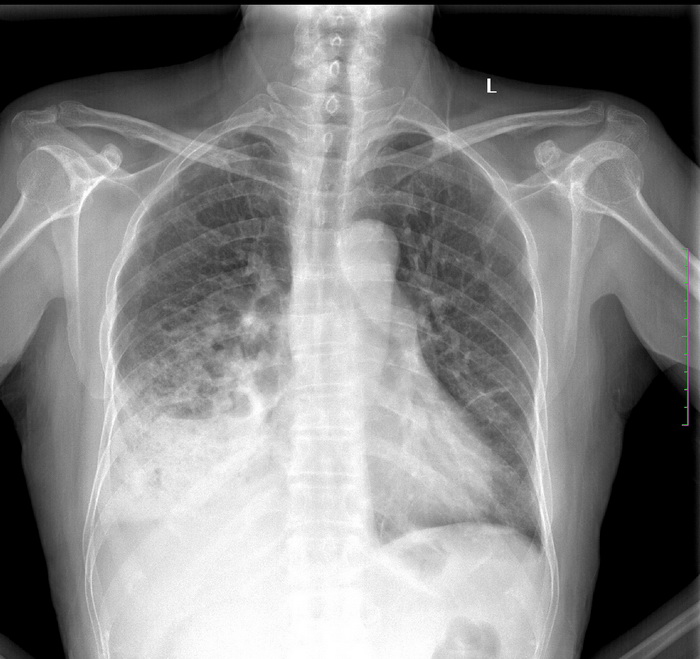

icu病人,几天都没明确诊断。m,76y,咳嗽、咳痰1周,伴气促,右胸痛入院,pe:t38.3c p135 r25 bp135/85。双肺可闻及大量湿罗音,心、腹未见明显异常。诊断:1心衰?2肺部感染?3冠心病?

9号平片